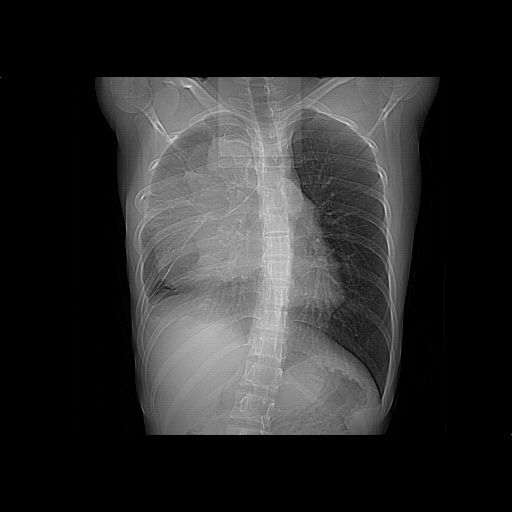

以下是引用zjzjr在2008-7-20 12:57:00的发言:[br]考虑为生殖源性肿瘤(内胚窦瘤),侵袭性胸腺瘤可能性大;右侧少量胸腔积液。

以下是引用xinliheng001在2008-7-20 21:17:00的发言:[br]右纵隔巨大分叶状软组织均质密度肿块,右上肺叶受压明显,纵隔右移、胸膜受累有少量积液和结节样增厚。应增强扫描一定会有更具诊断价值的信息。

以下是引用xinliheng001在2008-7-20 21:17:00的发言:[br]右纵隔巨大分叶状软组织均质密度肿块,右上肺叶受压明显,纵隔右移、胸膜受累有少量积液和结节样增厚。应增强扫描一定会有更具诊断价值的信息。